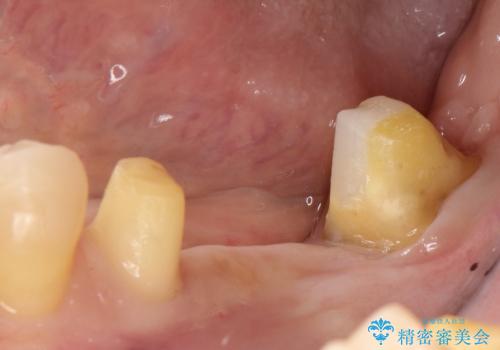

そのため、左下8を抜いて、左下7を部分矯正で後ろに起こしてからブリッジを新製することとしました。

最初にもともとのブリッジを壊し、矯正用の仮歯にかえた上で部分矯正を開始しました。

部分矯正期間はだいたい3か月弱です。